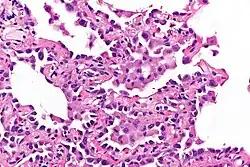

Microscopy

- Well-demarcated, nodular lesions ranging 2–5 mm in pulmonary parenchyma.

- Type II pneumocytes without nuclear atypia lined thickened alveolar septa and proliferated papillary structures.

- Enlarged cuboidal cells lining mildly thickened alveolar septa.[11]

- Enlarged cuboidal cells have abundant, eosinophilic cytoplasm and large, round nuclei.[12]

- Papillary pattern with irregular margin and lymphocyte infiltration in the stroma.[13]

- No proliferation of immature smooth muscle cells suggestive of lymphangioleiomyomatosis.